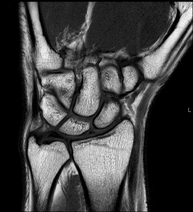

Exploració per a l'estudi de lesions en els tendons, els músculs i les articulacions. Molt útil per a la valoració de petites fractures inadvertides, lesions de lligaments i processos inflamatoris i degeneratius (artritis i artrosi). La durada aproximada és de 20 minuts. No utilitza radiació ionitzant. - RM de Mà / dits

Exploración para el estudio de las lesiones en pequeñas estructuras anatómicas de sus articulaciones tales como ligamentos y cartílago. El estudio viene precedido por una inyección de contraste en el interior de una de las articulaciones, realizada bajo control de rayos X. La duración global de los dos procedimientos es de 50 minutos. - Artro-RM Cadera